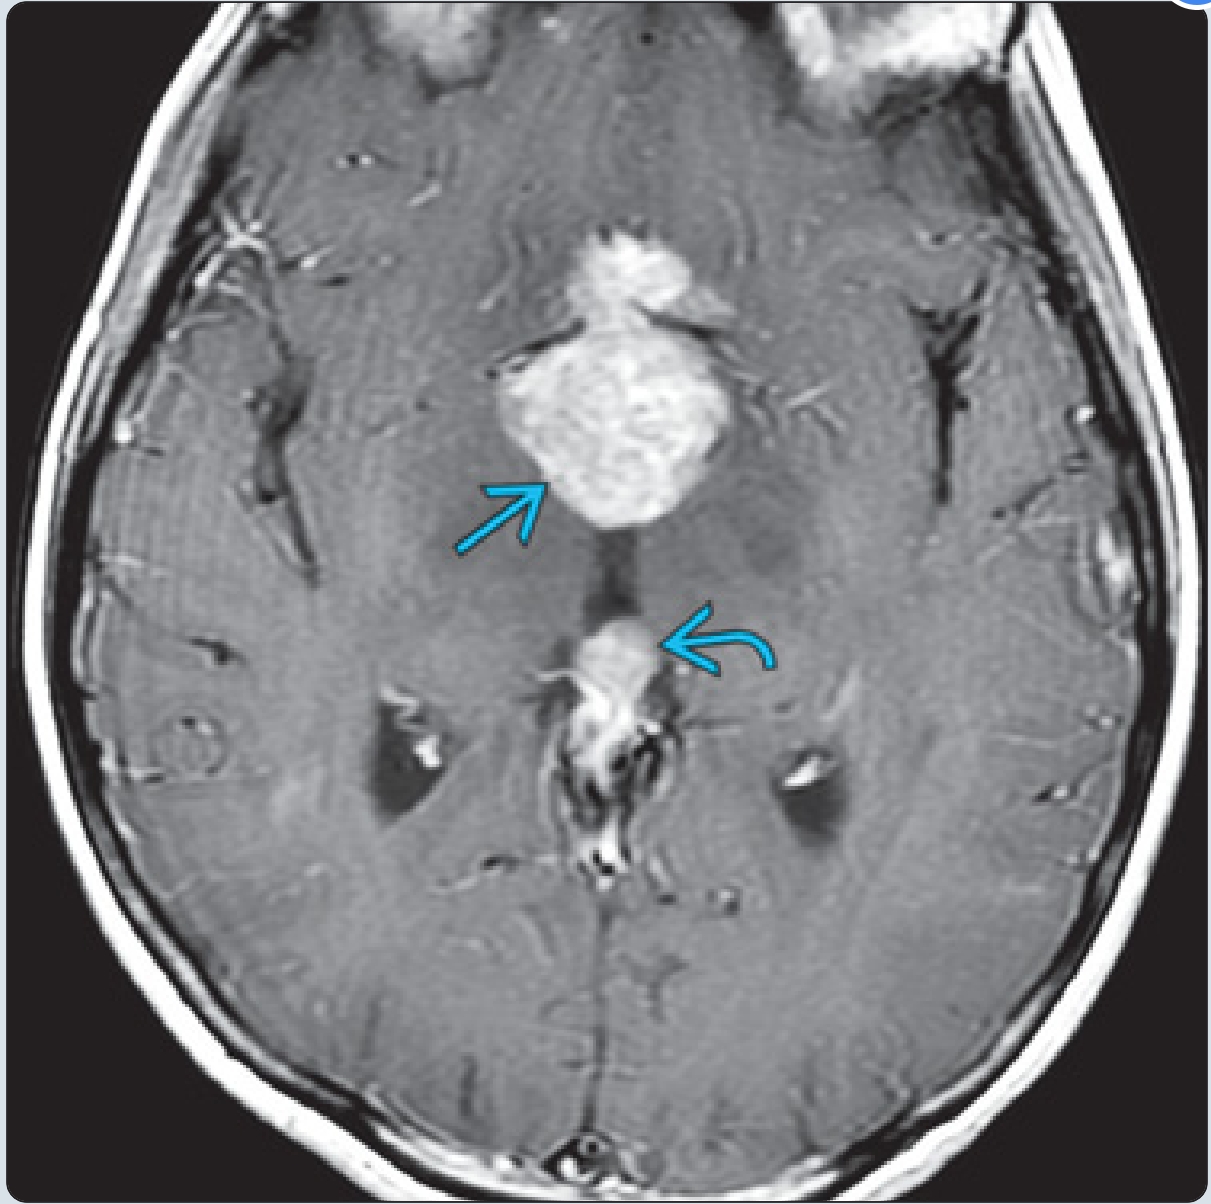

同一患者的T1 C+示鞍上病变明显强化。松果体也均匀增大。约20%的病例合并有鞍上和松果体肿块(有时称为“双中线”生殖细胞瘤)